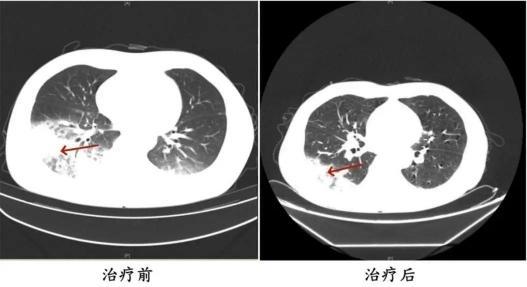

周先生治疗前后的肺部CT影像